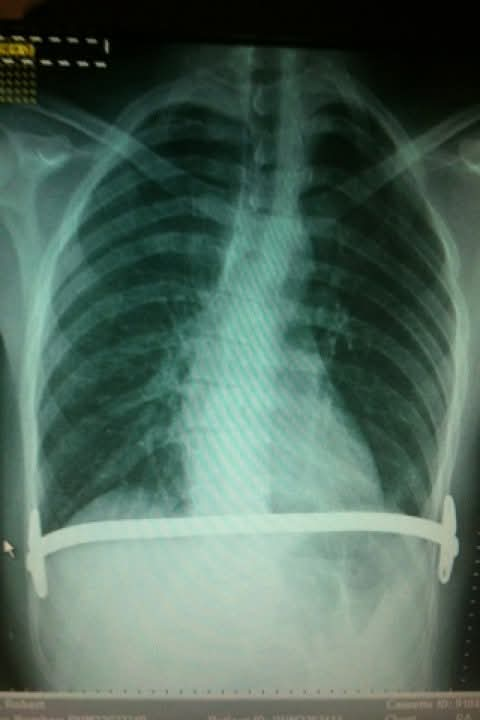

So far, the money raised has helped him get another X-ray, which revealed his spine has become more curved and his oesophagus is being crushed in multiple places, exacerbating the symptoms of the hernia.

In Mr Lindsell’s case, he required surgery, and when he was aged 22, he was given the Nuss Procedure. It involves placing one or more stainless steel bars into the chest to alter the position of the breastbone. These bars are left on for two or three years before being removed.

Mr Lindsell said that because he has scoliosis, he faced complications and now believes the surgery was not suitable for his condition.

“It's an ‘S shaped’ scoliosis, so it causes my body to twist tightly, and with that, the procedure on the left-hand side stayed exactly where it should. But on the right, my chest falls backwards and to the side, so it actually fits underneath my armpit and then presents itself as a bit of a hunch on my back,” he explained.